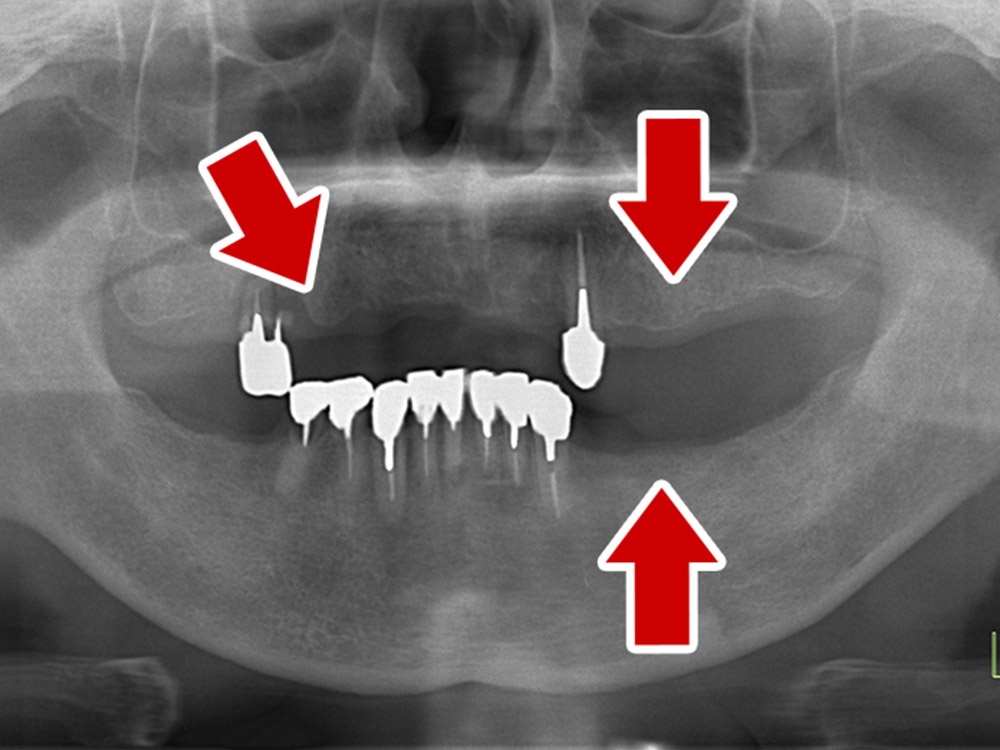

症例紹介

- 主訴

- 入れ歯が合わない。食べにくい。人生を豊かにしたい。

- 処置内容

- 上顎4本で12歯(オールオン4)、下顎4本5歯。

上下抜歯即時埋入、即時荷重(手術当日にインプラントの上に仮歯装着)

- 治療費用

- 上顎:約290万(税込)、下顎:約210万円(税込)

- 治療期間・通院回数

- 上顎:9か月/9回

下顎:6か月/7回

- リスク

- 術後の腫れ、痛み(ピークは3日後、1週間で軽減)

上部構造物、仮歯の破折、人工歯根脱落リスクがあります